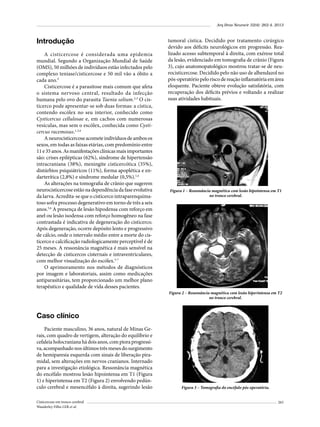

10 to 70 years, with a mean age of 42,5 ± 12,4 years (Figure

Figure 1 – Age of 58 patients diagnosed with GH secreting pituitary adenomas.